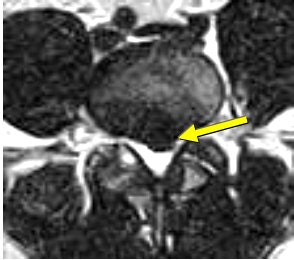

![]() |

| Above, preaxial loaded. Below, axial-loaded image. Central subligamentous disk herniation and discogenic disease at L5-S1 impressing the thecal sac only after axial loading is applied. L4-L5 bulging, discogenic disease, and a central subligamentous disk herniation impressing on the thecal sac. Bulging and discogenic disease at all other levels. |